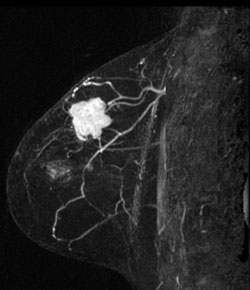

MIP (Maximum Intensity Projection) image of MR

MIP (Maximum Intensity Projection) image of MR shows the known cancer: irregularly marginated mass in the upper outer to central breast. Satellite subcentimeter nodules are present anteromedially and posteriorly.